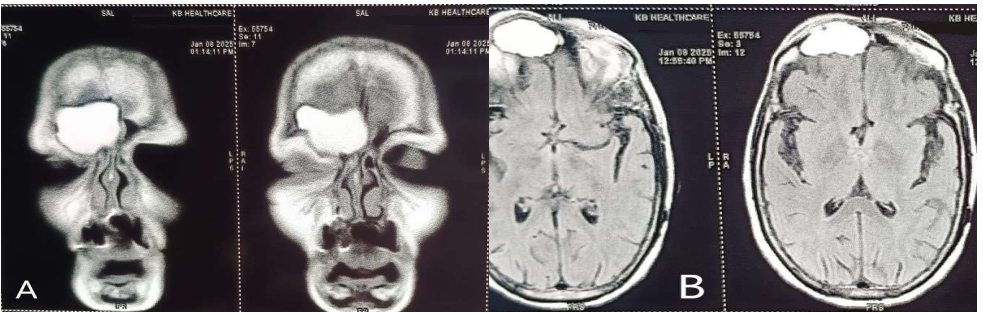

Huge Frontal Sinus Mucocele in an Immunocompromised Patient

Mucoceles of the paranasal sinuses are defined as cystic expansile lesions (Lageback in 1820). Rollet in 1909 coined the term mucocele. Mucocelesare most commonly found in the frontal sinus (60–65%) butcan also occur in ethmoidsinuses (around 25%), sphenoid sinus (1–2%) and maxillary sinus (10%). The etiopathogenesis of PNS mucocele is multifactorial with most common causes being allergy, inflammation and trauma or less commonly it can be secondary to neoplastic lesions in PNS which are obstructing the sinus ostia.